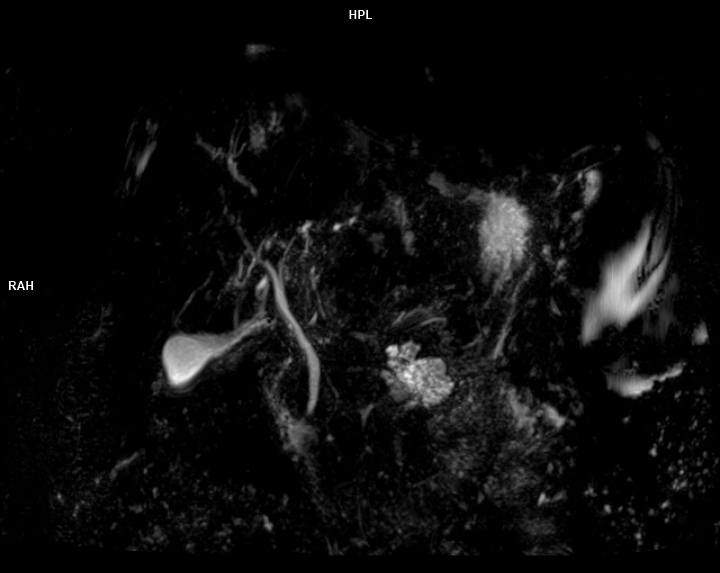

• 3 TESLA MR ÇEKİM GÖRÜNTÜLERİ

3 Tesla MR Çekim Görüntüleri

• 3 Tesla MR Çekim Görüntüleri